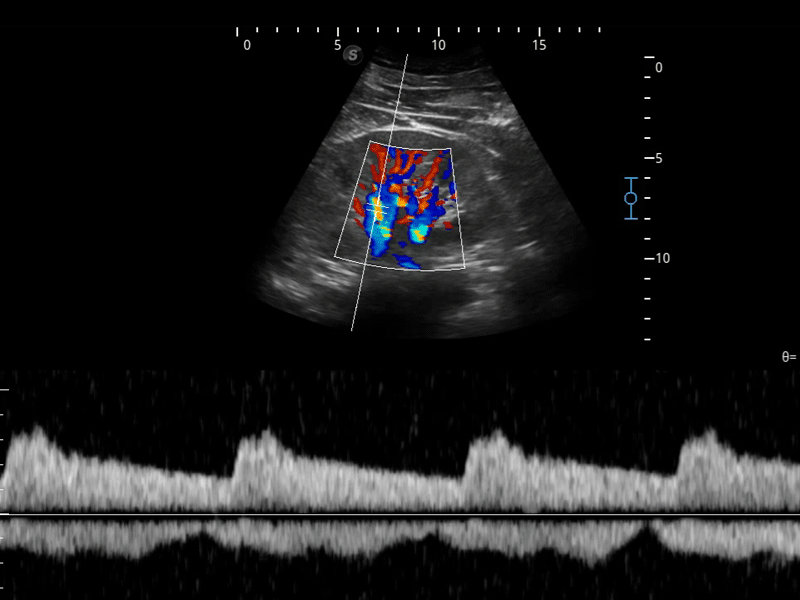

SR Flow高分辨率血流成像

高分辨率血流成像技术提高了对低速血流信号的检测能力。在提高空间分辨率的同时,也克服了血流外溢现象,为用户提供更加真实的血流动力学信息。

组织多普勒

组织多普勒成像功能,可提供心肌运动速度和其他临床信息,使临床医生能够分析和比较患者心脏不同部位的运动。